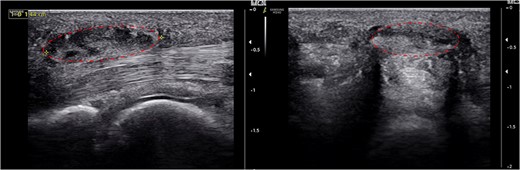

Plain radiography revealed no abnormalities: 1.5 cm-sized hyperechoic mass without vascular invasion above thickened A1 pulley of RRF was observed on ultrasonography. There was severe tenderness around A1 pulley area as well as triggering of flexor tendon during passive flexion and RRF extension (Fig. 1).

About 1.5 cm-sized hyperechoic mass (dotted circle) around the thickened A1 pulley and flexor tenosynovitis was detected.